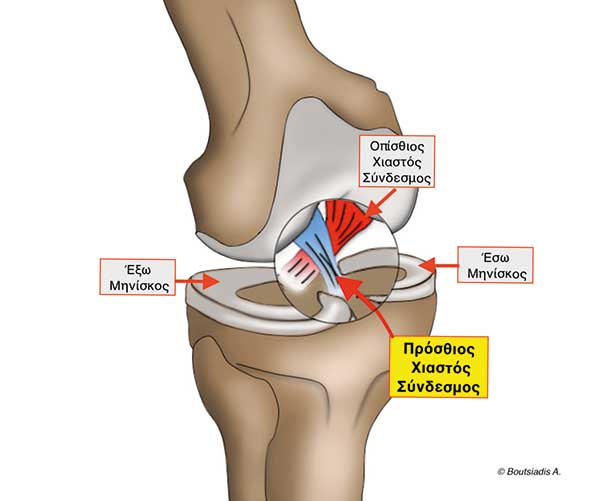

Η συνδεσµοπλαστική του προσθίου χιαστού συνδέσµου είναι µια ευρέως διαδεδοµένη ορθοπαιδική εγχείρηση µε περίπου 400.000 νέα περιστατικά παγκοσµίως κάθε έτος που στόχο έχει να αποκαταστήσει έναν από τους κυριότερους σταθεροποιητικούς παράγοντες του γόνατος. Η φυσιολογική ανατοµία του προσθίου χιαστού συνδέσµου φαίνεται στην Εικόνα 1.